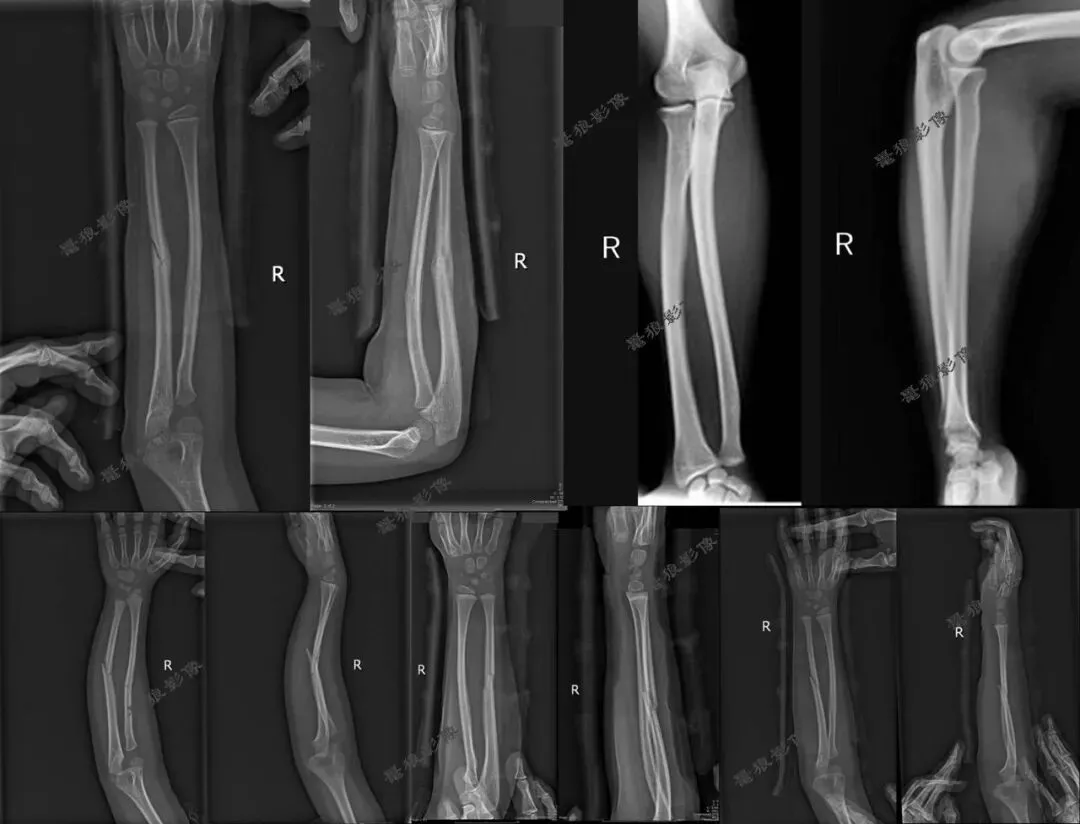

七、需要警惕以下情况发生

一、难道桡尺骨正侧位就必须全部伸直肘部或者全部弯曲肘部90°拍摄?说到底还是因为这样拍摄是标准的,有利于诊断。

三、假如说病人是靠近腕关节那一侧的桡尺骨有问题时,我们拍摄桡尺骨正侧位也只包括一侧腕关节时,这样的拍摄方法(全部伸直或者全部弯曲)也许不会发现此问题。但是病人是肘关节那一侧的桡尺骨有问题时,我们拍摄桡尺骨必须要包括肘关节时,这样的拍摄方法(全部伸直或者全部弯曲)就有问题啦!桡尺骨侧位片伸直显示不出肘关节侧位,桡尺骨正位片弯曲90°显示不出肘关节正位,我们都没法查看肘关节的解剖细节!